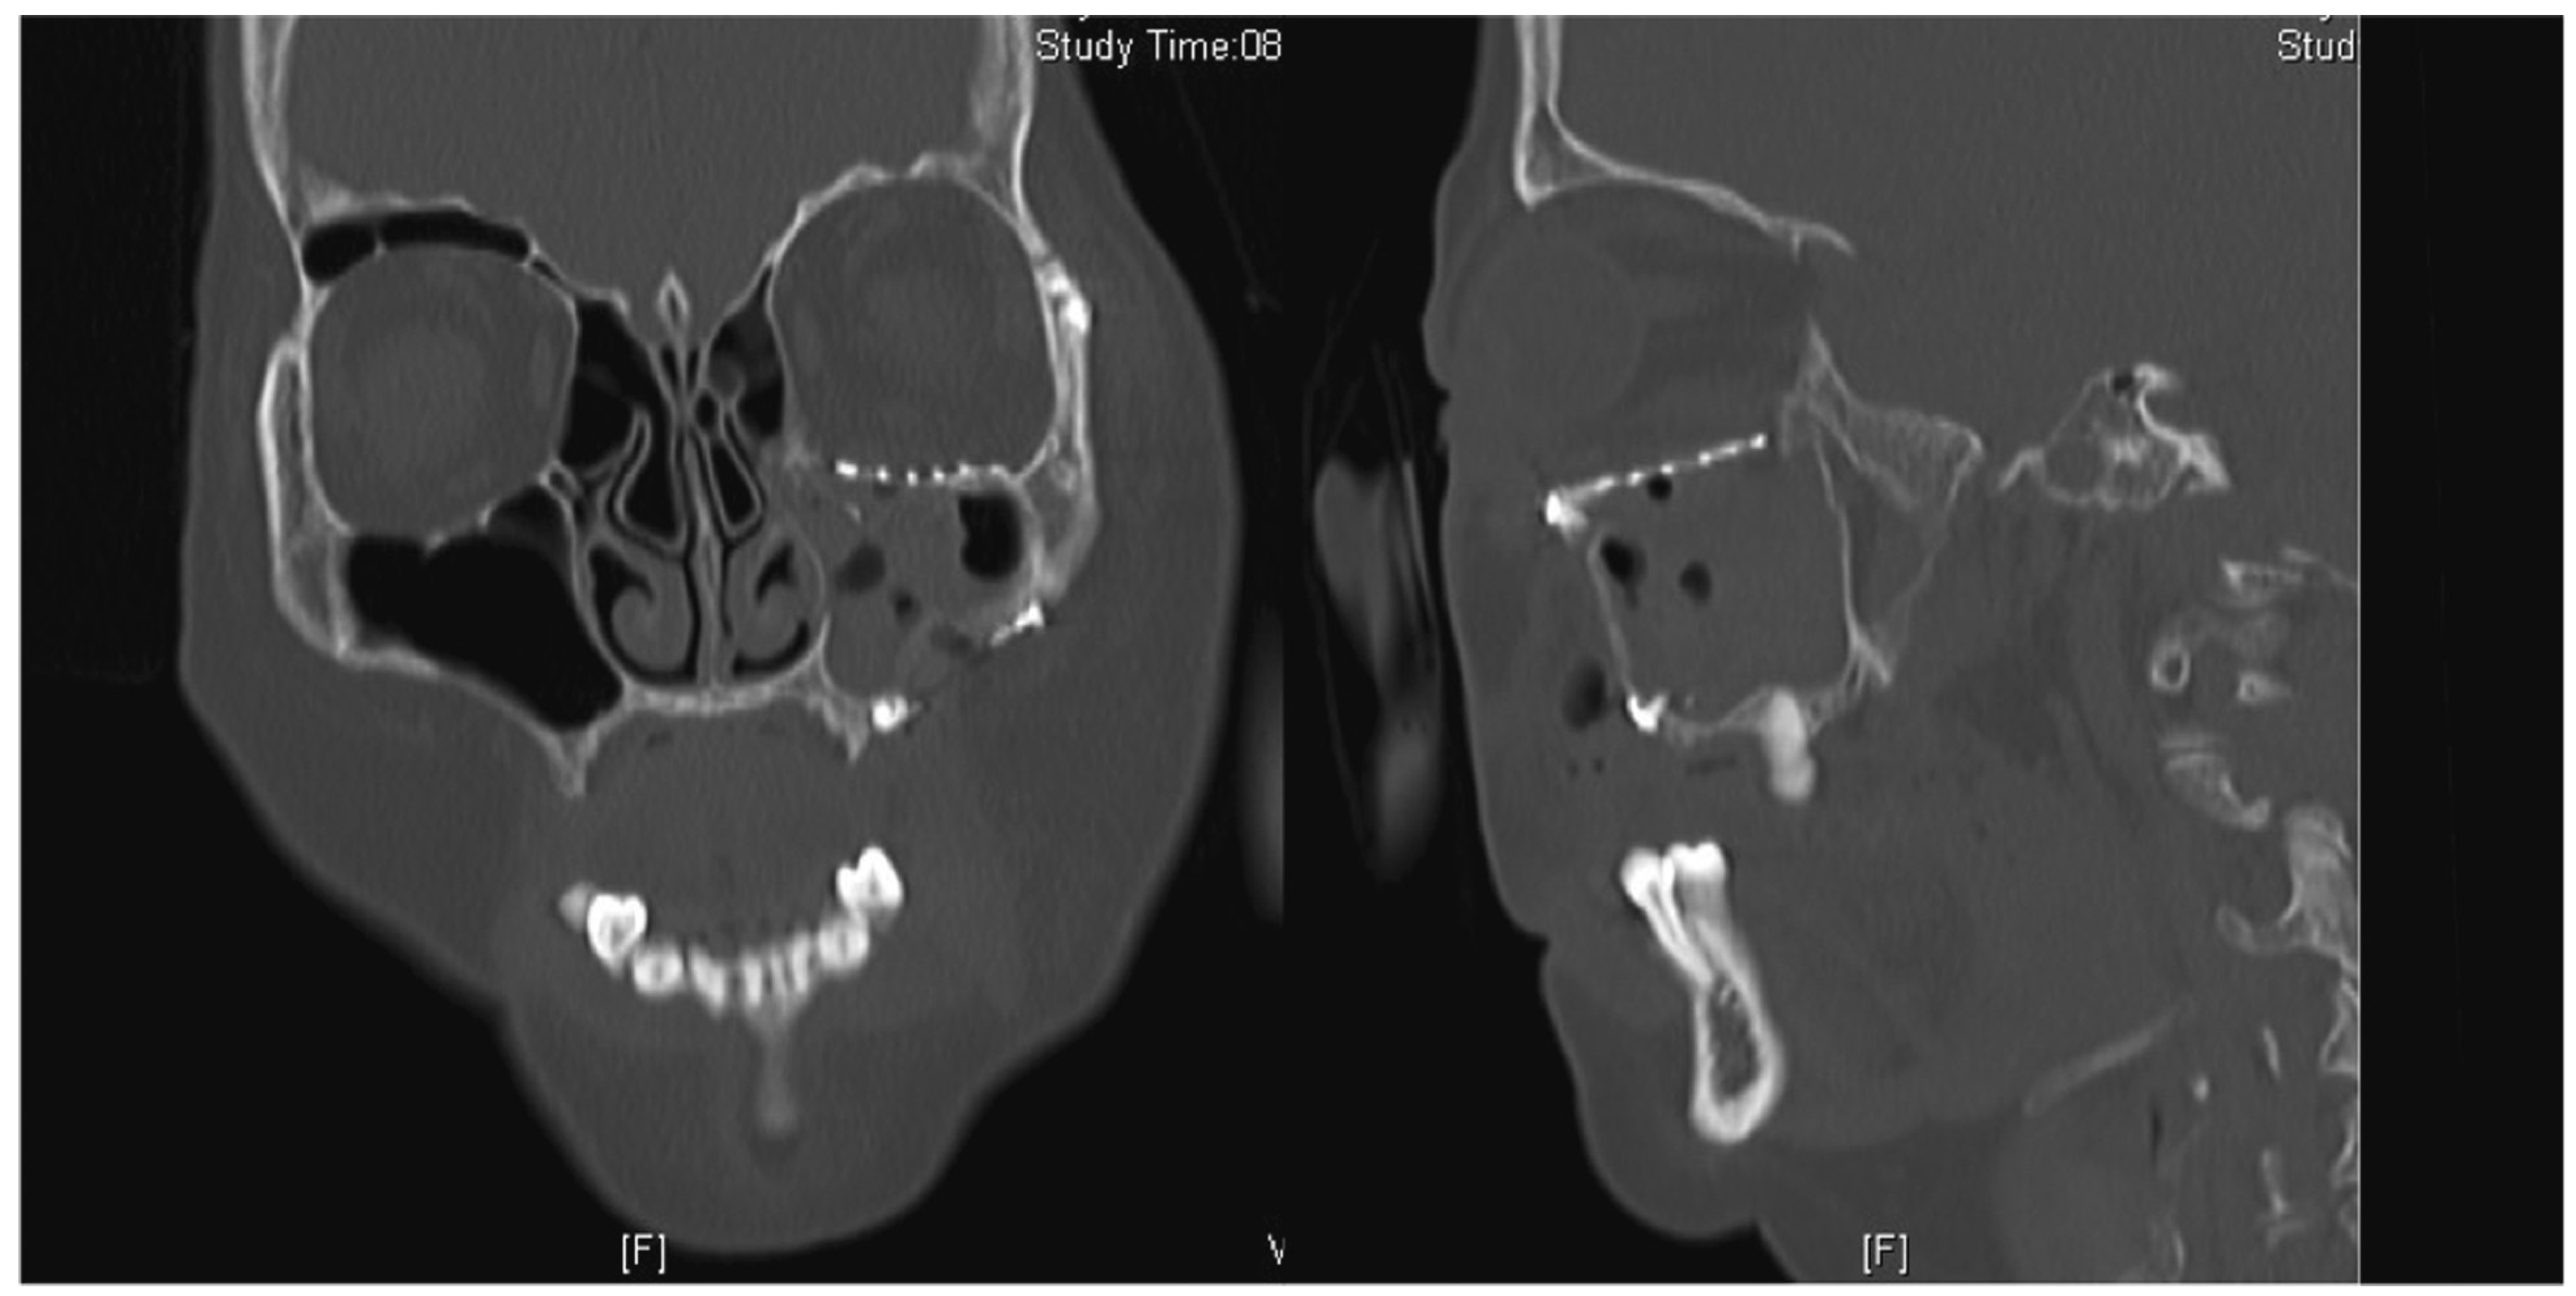

The surgery took place 10 days following the accident due to neurosurgical concerns regarding his brain injury. Intraoperatively, the periorbita surrounding the herniated contents was noted to be disrupted. A 0.4-mm titanium curved plate was used to reconstruct the orbital rim, and the medium 0.4-mm precontoured titanium orbital plate (Figure 2) was used for reconstruction of the orbital floor defect (DePuy Synthes, Johnson & Johnson, Solothurn, Switzerland). Intraoperatively, he had a negative forced-duction test and postoperatively, he was noted to have full range of extraocular movements of his right eye. The postoperative CT scan demonstrated anatomical placement of the orbital floor plate with reduction of all periorbita (Figure 3).

Figure 3. Coronal and sagittal cuts of the postoperative CT scan of the face (Case 1) demonstrating reduction of all periorbita.